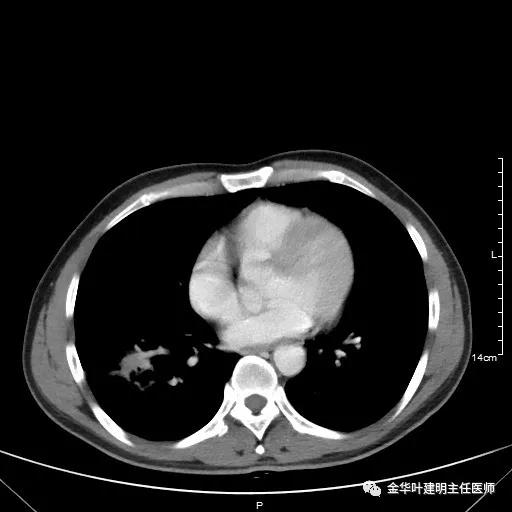

如果选取肿瘤所在的层面来看,则是以下图像:

以上是肺窗,见右肺下叶实性占位,有毛刺、浅分叶、膨胀性,血管征等,是较为典型的恶性肿瘤。

以上为纵隔窗,可见纵隔内未见显著增大的转移性淋巴结。